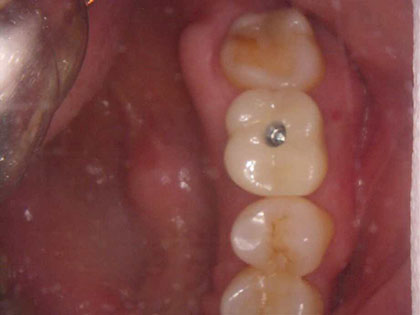

• 治療完了時の写真がこちら

• インプラント治療完了時1

• インプラント治療完了時2